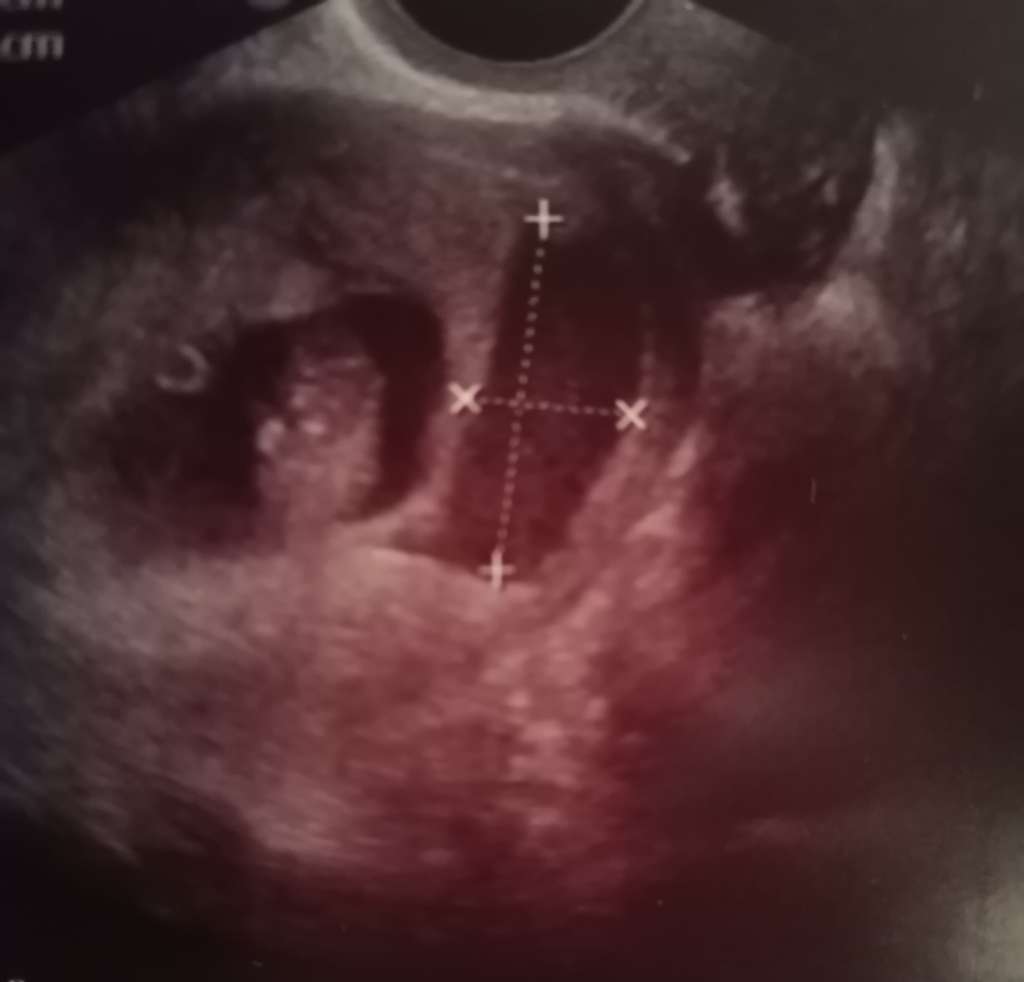

Myślę, że zdecydowanie jest inaczej ale należy pamiętać, że ogólnie każda ciąża trochę inaczej sobie radzi. Ja mialam krwiaka giganta wrzucę Wam fotkę i zaplamilam 2 razy tylko po usg, a po tym usg co był tako gigantyczny nie plamiłam w ogóle i cały się wchlonal. A są dziewczyny co mają malutkie krwiaczki i z jakiegoś powodu im się opróżniaja i bach krwawienie.

Ale tutaj to odklejenie mi wygląda właśnie na małego krwiaka i jak on się wchlonie alno oprozni to kosmowka powinna wrócić na swoje miejsce.

A tu mój krwiak po lewej ciąża po prawej krwiak 😅

• 3123ffca-8815-4169-b095-0612f7bb2d2a.jpeg

3123ffca-8815-4169-b095-0612f7bb2d2a.jpeg

26,1 KB · Wyświetleń: 265